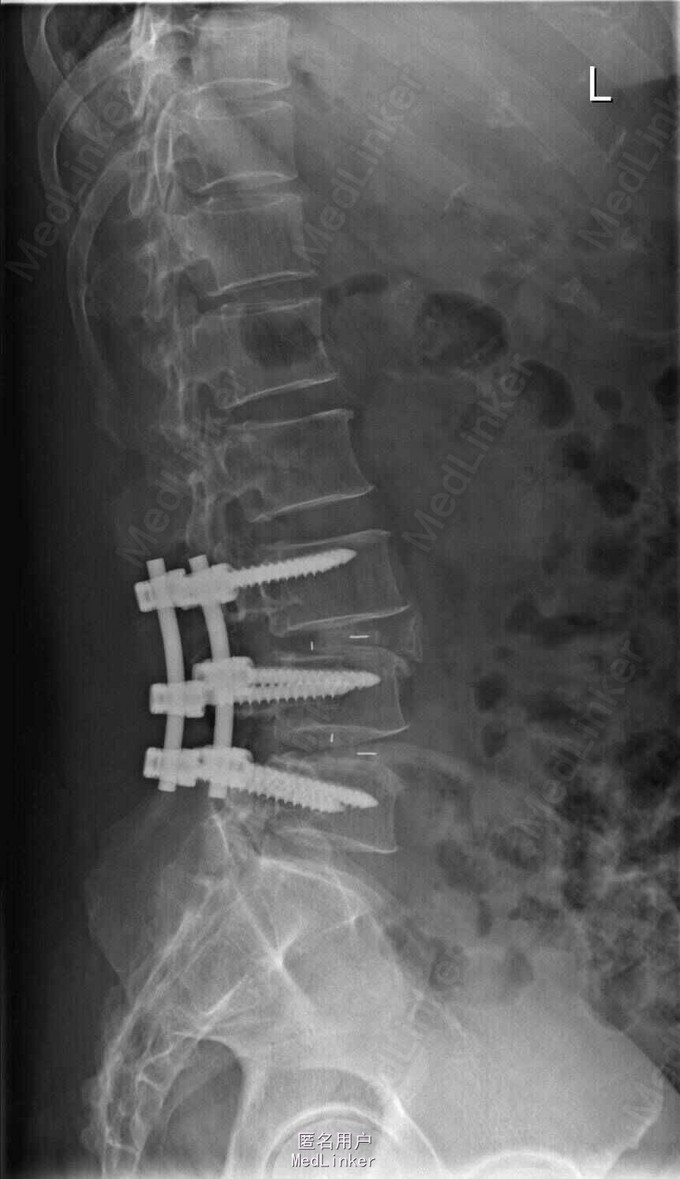

诊断:L3-4.L4-5椎间盘突出,椎管狭窄 治疗: 腰椎后路减压融合内固定术

术后麻木症状缓解,术后三月复查时,内固定装置位置良好,患者症状明显好转,行走后腰部稍酸胀,无腿部酸胀疼痛感。 讨论:外科病人术后随访较困难,病情好的较远的患者不再复诊,有何方法改善失访率?